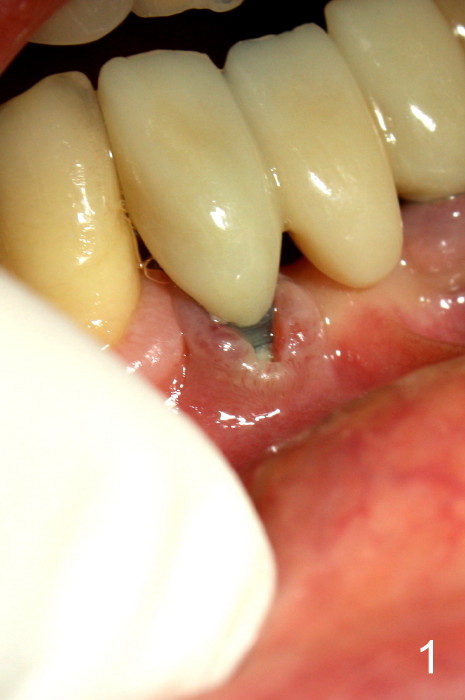

The patient has had chronic pain and swelling associated with the implant at the site of #26 (Fig.1). The extent of implant thread exposure is shown in Fig.2 after flap reflection; inflammatory granulation tissue is present around the most coronal threads (*, one year post cementation). Following debridement and Clindamycin soaking, allograft is placed around the exposed threads; a titanium mesh is used to contain the graft (Fig.3). The flap is closed with tension in spite of the periosteum being underscored. The patient develops moderate to severe ecchymosis postop.